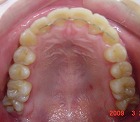

矯正前